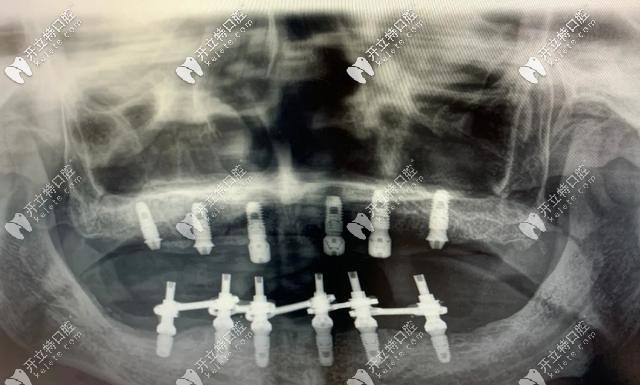

即刻負(fù)重種植牙主要針對(duì)全口無牙頜或半口無牙的情況下,每個(gè)半頜4-6顆種植牙就可以恢復(fù)半口的牙齒,術(shù)后2個(gè)小時(shí)即可戴牙進(jìn)食,實(shí)現(xiàn)了當(dāng)天種當(dāng)天用。

即刻負(fù)重種植牙對(duì)骨質(zhì)要求比較高,牙槽骨骨量得充足,種植體長(zhǎng)度大于10mm,直徑大于3.5mm,一般單顆牙缺失不適合即刻負(fù)重,適用于口內(nèi)多顆或全部牙齒缺失的人群。